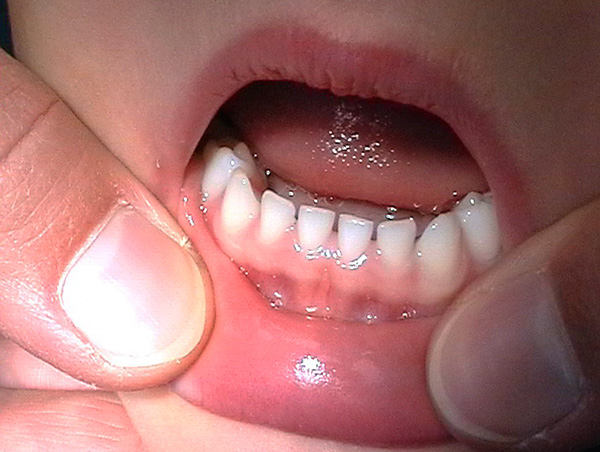

Gli ortodontisti prestano particolare attenzione al periodo del morso del latte tardivo, quando vengono effettuati i preparativi per la sostituzione dei denti temporanei con quelli permanenti. Già in questo momento, quando si esamina la cavità orale del bambino per una serie di segni (non sempre ovvi), si possono sospettare futuri problemi nella posizione dei denti.

Normalmente, la forma dei denti da latte coincide con la forma dei denti in un morso permanente, ma le corone dei denti temporanei dovrebbero essere proporzionalmente più larghe, specialmente nell'area dei molari temporanei (cioè, masticando i denti con i numeri 5 e 6). In questo caso, ampie corone preparano un posto per due futuri denti permanenti: i premolari.

A loro volta, gli incisivi temporanei (denti anteriori) hanno contorni più convessi e sono normalmente leggermente inclinati palatine, poiché le radici dei denti permanenti situati nell'osso esercitano una pressione sulle loro radici.

La dimensione dei denti e degli archi dentali del bambino è molto più piccola rispetto al periodo di un morso permanente. Nei bambini di età inferiore a 4 anni, la mascella inferiore occupa una posizione posteriore, ma quando inizia il periodo di crescita attiva delle mascelle e delle teste dell'articolazione temporo-mandibolare, la mascella inferiore si sposta in avanti (in parte ciò è dovuto alla natura dell'alimentazione del bambino - cessazione della suzione e masticazione attiva del cibo). Con la normale crescita delle mascelle tra i denti temporanei del bambino, compaiono lacune (tre) - questo indica il corretto sviluppo del sistema dentoalveolare e in nessun modo dovrebbe essere considerato come una patologia dai genitori (come talvolta accade).